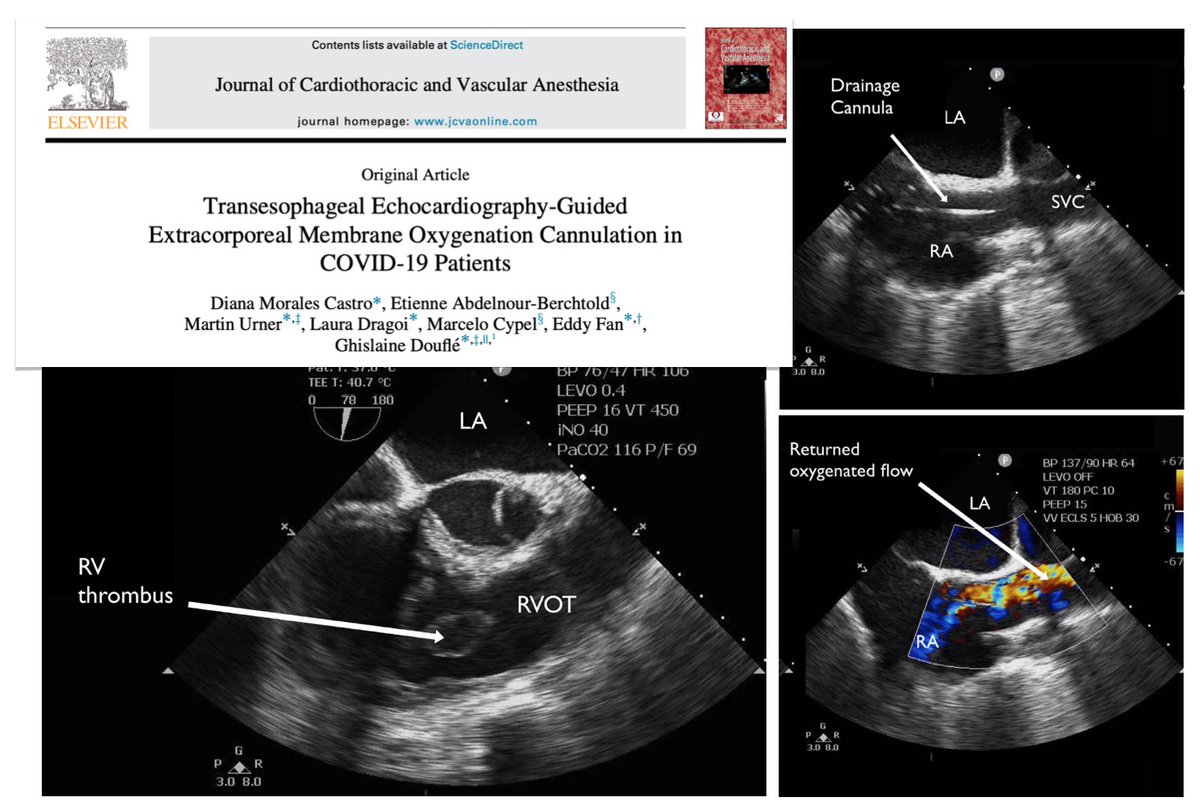

Complications on VV #ECMO... What can go wrong?? Lot of things... be aware of ➡️ patient selection ➡️ timing of ECMO or transfer to ECMO center ➡️ configuration ➡️ MV ➡️ weaning/decannulation ➡️ short term problems ➡️ long term sequelae @CritCareMed 🖇️ bit.ly/3S1L17E

A @COVIDcritical study reveals that for a subset of patients, use of #ECMO to treat #COVID-related respiratory failure is linked with a 7.1% reduction in death vs. mechanical ventilation alone. Congrats Drs. @efan75 @martin_urner and JF Fraser > bmj.com/content/377/bm… @UHN